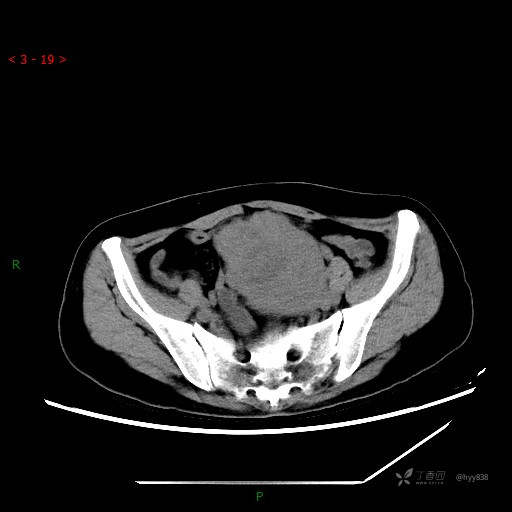

辅助检查:CT

盆腔CT平扫